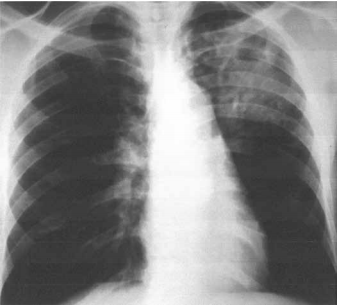

Homem de 27 anos de idade, sem patologias prévias, apresenta quadro de febre intermitente, anorexia, perda de 8 kg no período (12% do peso) e tosse há 2 meses. Nega uso de medicamentos, viagem recente, tabagismo, etilismo ou ingestão de drogas ilícitas. Exame físico: hemodinamicamente estável; FR: 24 ipm, saturação arterial de O2 : 87% e T: 38,1 ºC. Teste para o vírus HIV: negativo. A radiografia de tórax realizada é mostrada a seguir.

A principal hipótese diagnóstica é